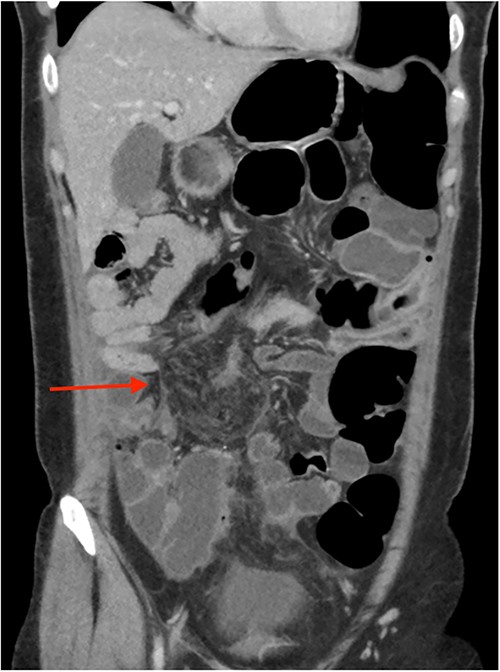

On review of imaging, we noted a CT scan from 2019 which showed swirling and stranding of omentum/mesenteric fat inferior to hepatic flexure (CC 1.8 cm, TV 2.6 cm), with suspicion of internal herniation of the omental/mesenteric fat leading to infarction (Figs 1 and 3). Management of this was unclear as this was at a private hospital in metropolitan Western Australia. A repeat CT scan during her current presentation revealed similar swirling of omentum/mesenteric fat, but with interval increase in size (CC 5.5 cm, TV 7.6 cm). There was associated small bowel dilatation and wall thickening and enhancement with no focal transition point (Figs 2 and 4).

Second, omental torsion is rarely managed conservatively with surveillance imaging. Hence, it is rare that we have CT imaging showing the progression of omental torsion over 4 years, noting the markedly increased dimensions and characteristic mesenteric swirling.